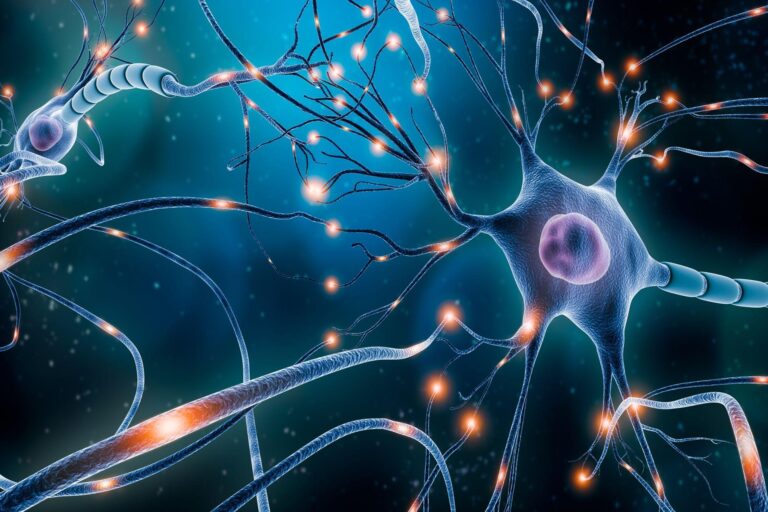

الإماراتباحثون من جامعتي “نيويورك أبوظبي” و”دنفر” يطورون تقنية تدعم علاجات أمراض الدماغأبريل 2, 2026